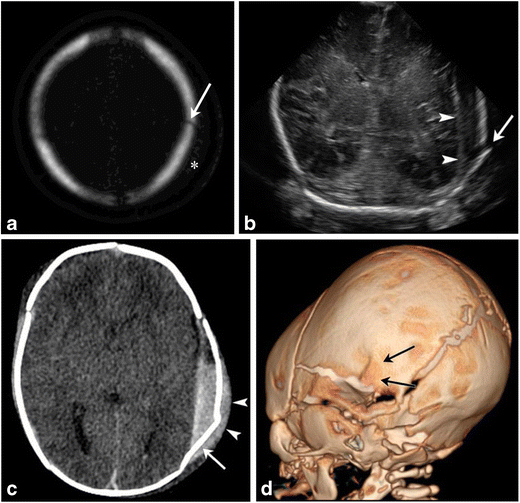

Mechanical Birth Related Trauma To The Neonate An Imaging